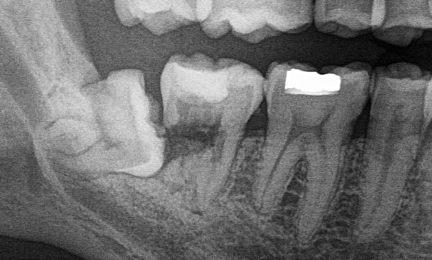

Bite-wing, alebo po slovensky aj záhryzová snímka, vie skvele odhaliť kazy medzi zubami alebo pod plombami, ktoré inak sa nedajú v ústach vidieť.